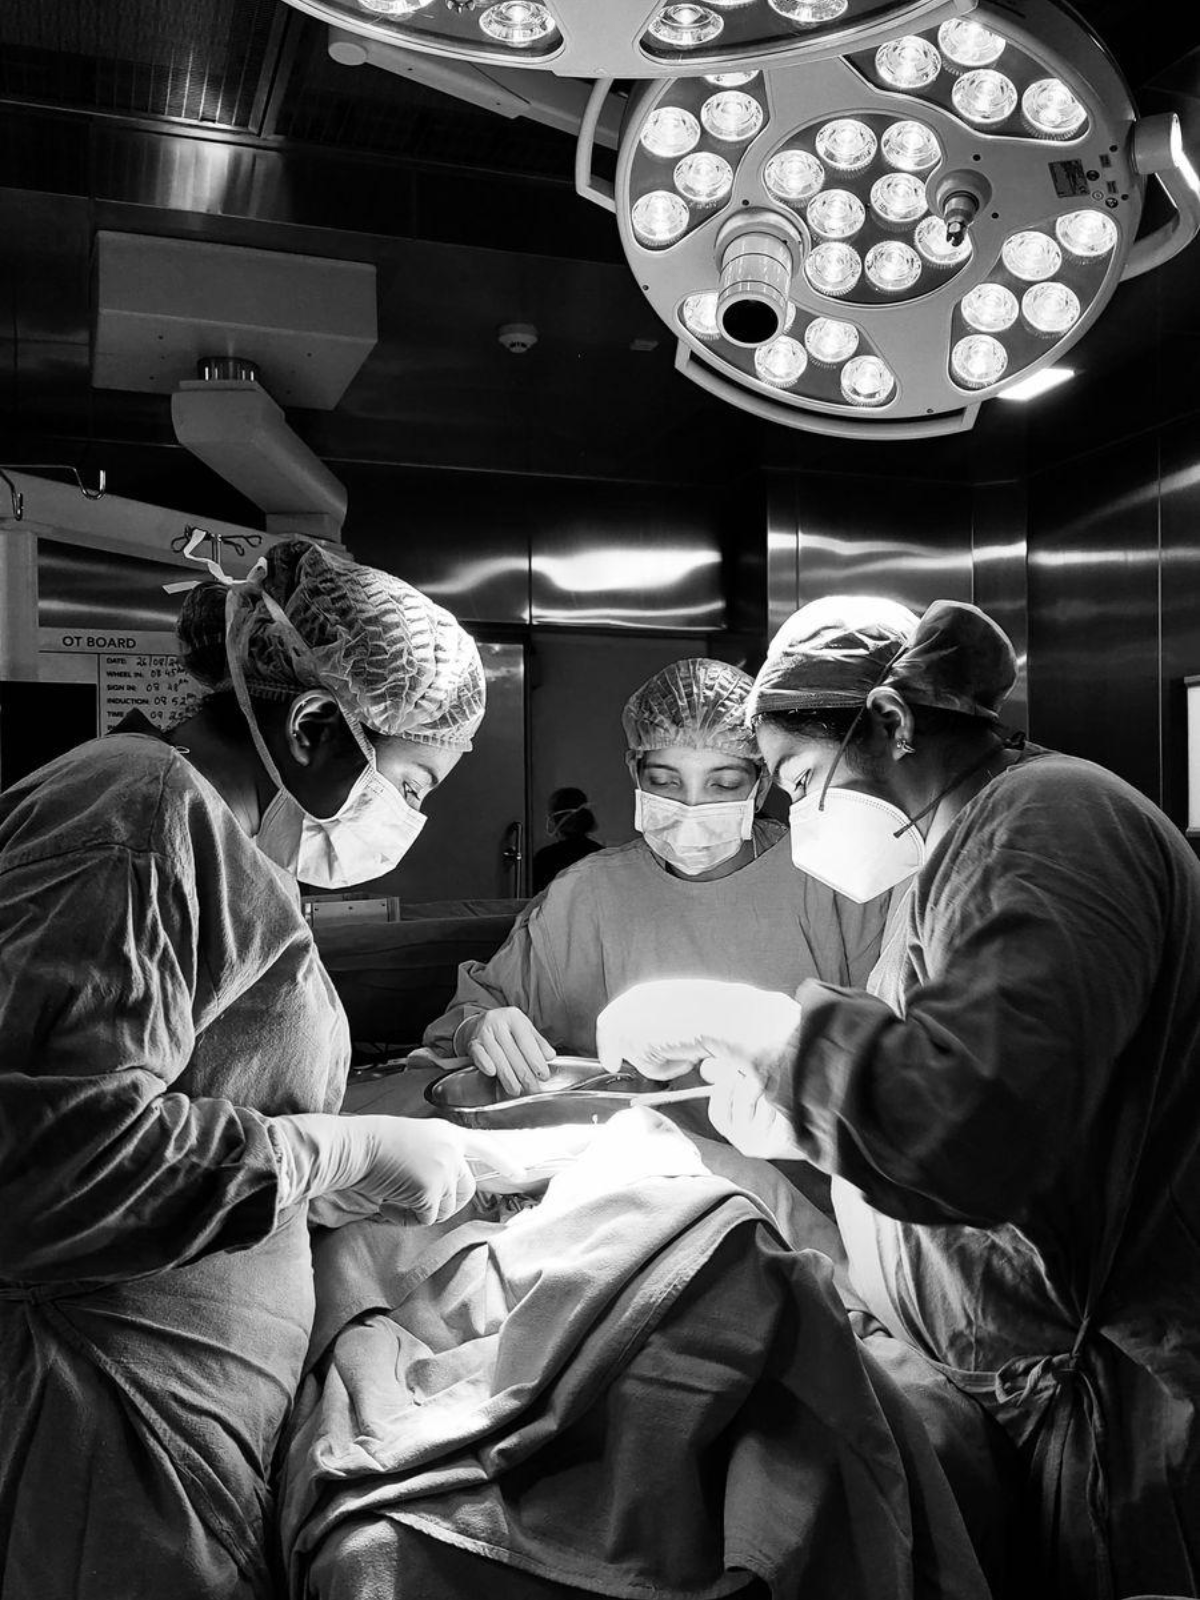

Dr. Reshma – Oral and Maxillofacial SurgeonI am Dr. Reshma, a dedicated Oral and Maxillofacial Surgeon with expertise in a wide range of surgical and aesthetic procedures. Having completed my BDS and MDS in Oral and Maxillofacial Surgery, I am committed to delivering advanced surgical care with precision, expertise, and compassion.

Our Work Speaks for Us

Discover our exceptional work, showcasing precision, expertise, and transformative results in oral, maxillofacial, and aesthetic procedures.